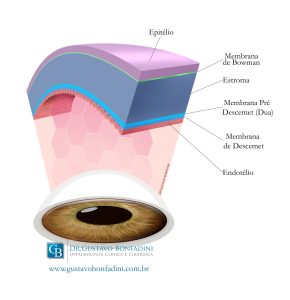

Modelo esquemático das 6 camadas da Córnea:

No protocolo tradicional de Crosslinking, o procedimento é realizado em um centro cirúrgico, e após anestesia tópica (com colírio), o Epitélio, camada mais externa da Córnea, é removido. Na sequência gotas de Riboflafina (Vitamina B2 – que funciona como substância foto-sensibilizadora) são aplicadas na córnea por 30 minutos para que penetre no estroma, camada de sustentação da córnea. Após a verificação da saturação da camada do Estroma da Córnea, procede-se com a aplicação de radiação ultravioleta A (UVA) por 30 minutos, com comprimento de onda de 370 nm e 3mW/cm2. Durante esta etapa mais gotas de vitamina B2 são utilizadas.